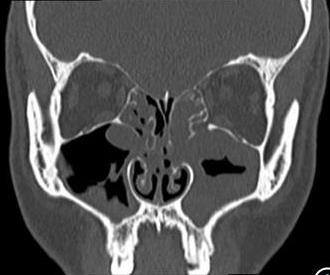

• 术前规范化药物治疗对鼻内镜下慢性鼻窦炎伴鼻息肉患者术后鼻黏膜重塑的影响

摘要:目的 探讨术前规范化药物治疗对鼻内镜下慢性鼻窦炎(CRS)伴鼻息肉(CRSwNP)患者术后鼻黏膜重塑的影响。方法 选取2022年1月-2023年6月该院收治的CRSwNP患者80例,根据随机数表法将患者分为观察组(n = 40)和对照组(n = 40),对照组给予功能性鼻内镜手术治疗,观察组在对照组的基础上给予术前规范化药物综合治疗。比较两组患者鼻腔黏液纤毛清除功能、鼻功能和鼻黏膜重塑变化;采用广义估计方程(GEE)模型,分析其改善情况;采用多元线性回归模型,分析其与各评分之间的关系;采用双重差分模型,分析治疗效果。结果 两组患者组内不同时点(治疗前、治疗后3个月和治疗后6个月)的糖精清除时间、鼻黏液纤毛清除率、黏液纤毛清除速率、鼻腔容积(NCV)、鼻腔最小横截面积(NMCA)、最小横截面积距前鼻孔距离(DCAN)、嗜酸性粒细胞(EOS)、转化生长因子β1(TGF-β1)和血管内皮细胞生长因子(VEGF)水平比较,差异均有统计学意义(F = 124.36,P = 0.000;F = 113.58,P = 0.000;F = 98.67,P = 0.000;F = 87.37,P = 0.000;F = 107.26,P = 0.000;F = 77.45,P = 0.000;F = 3.80,P = 0.008;F = 2.56,P = 0.012;F = 2.13,P = 0.015);观察组治疗后3和6个月糖精清除时间较对照组短,鼻黏液纤毛清除率较对照组高,黏液纤毛清除速率较对照组快,NCV和NMCA较对照组大,DCAN较对照组短,EOS、TGF-β1和VEGF水平较对照组低,差异均有统计学意义(F = 44.36,P = 0.000;F = 38.23,P = 0.000;F = 30.44,P = 0.000;F = 27.33,P = 0.000;F = 36.11,P = 0.000;F = 22.00,P = 0.000;F = 2.44,P = 0.014;F = 1.89,P = 0.017;F = 1.75,P = 0.021);两组患者糖精清除时间、鼻黏液纤毛清除率、黏液纤毛清除速率、NCV、NMCA、DCAN、EOS、TGF-β1和VEGF水平变化趋势比较,差异均有统计学意义(F = 18.33,P = 0.000;F = 15.78,P = 0.000;F = 13.00,P = 0.000;F = 8.17,P = 0.002;F = 10.23,P = 0.000;F = 4.34,P = 0.004;F = 2.89,P = 0.013;F = 1.67,P = 0.022;F = 1.43,P = 0.031)。GEE分析结果显示,观察组鼻黏液纤毛清除率、黏液纤毛清除速率、NMCA、NCV、DCAN和糖精清除时间的改善情况明显优于对照组,差异均有统计学意义(P < 0.05);治疗后6个月,两组患者Lund-Kennedy评分、Lund-Mackay评分和鼻腔鼻窦结局测试-20(SNOT-20)评分明显低于术前,且观察组明显低于对照组,差异均有统计学意义(P < 0.05);多元线性回归模型分析结果显示,糖精清除时间、DCAN、EOS、TGF-β1、VEGF水平、鼻黏液纤毛清除率、黏液纤毛清除速率、NCV和NMCA与Lund-Kennedy评分、Lund-Mackay评分和SNOT-20量表评分密切相关(P < 0.05)。双重差分模型结果显示,观察组Lund-Kennedy评分、Lund-Mackay评分和SNOT-20量表评分的改善情况明显优于对照组。观察组总有效率为92.50%,明显高于对照组的75.00%,差异均有统计学意义(P < 0.05)。结论 在鼻内镜术前采用规范化药物治疗,可以有效地促进CRSwNP患者鼻黏膜修复,抑制术后鼻腔重塑,且疗效较好,值得临床推广应用。